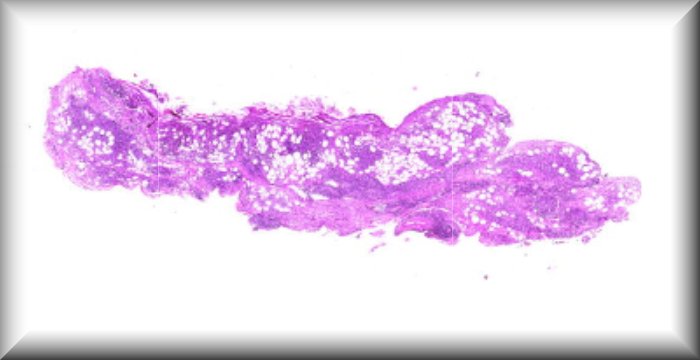

Luis Alfaro: A 65-year-old woman with a rapidly growing tumor in the upper left eyelid |